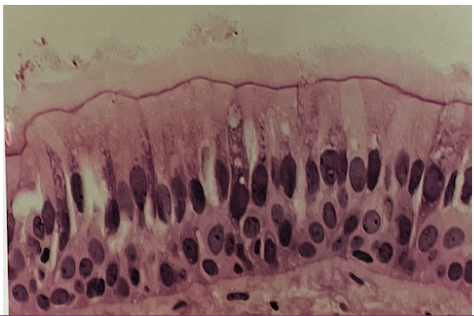

pesudostratified (ciliated)